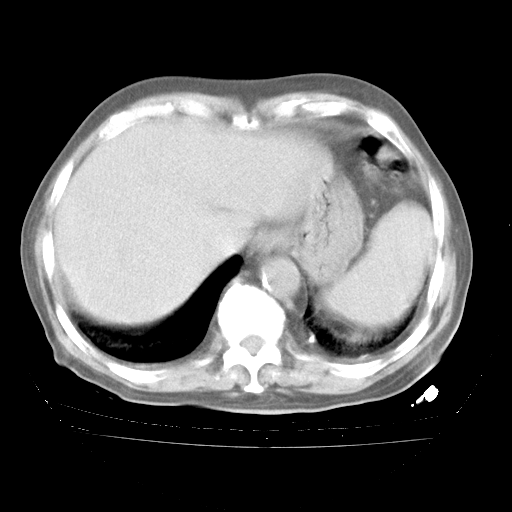

今天部分检查

轻微咳嗽,无痰,(体温正常时)R20次/分,P75次/分,双肺底、腋下可闻及少量捻发音。下肢轻度浮肿。

腹部B超:胆囊壁增厚,肝、胆、胰、脾、肾无异常,肠系膜淋巴结、腹膜后淋巴结无增大。

增加治疗:异烟肼、利福平、乙胺丁醇,静滴左氧氟沙星、参麦注射液。甲强龙从80mg暂减为40mg。

强的松3月1日改为10mg qd,4月1日改为10mg qod。3月份以前的减量过程和环磷酰胺疗程需等明天查看记录(我岳父自己做的记录在他家里)。